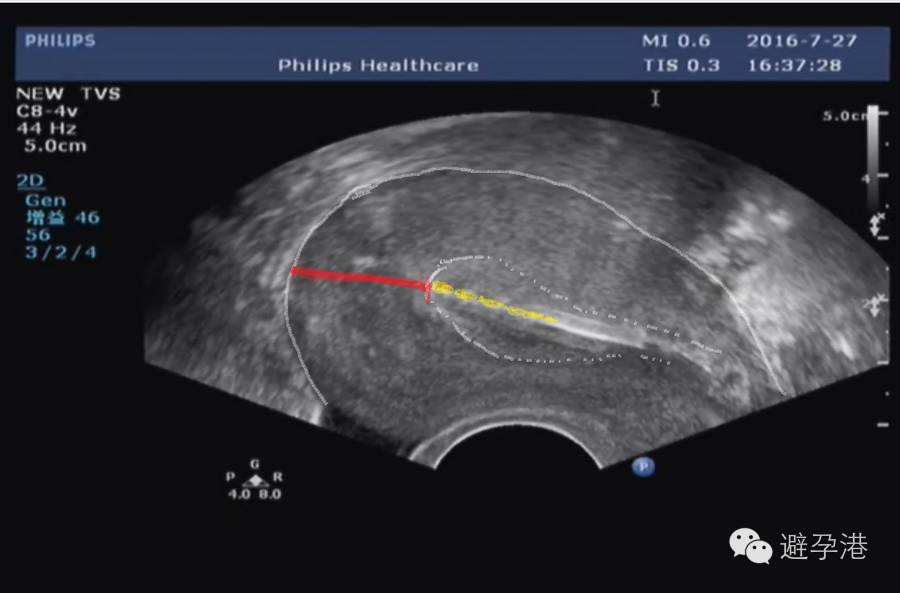

1.吉妮致美是固定式避孕环,放置成功后极少发生脱落下移。超声定位重点在于观察吉妮致美所在位置是否安全,即观察吉妮致美第一个铜套上缘到子宫浆膜层的(S-S)距离。

吉妮致美环怎么样吉妮致美节育器超声图像解读_https://www.jmylbn.com_新闻资讯_第8张

2.定位宜切扫描观察:

①S-S≤1.1cm,为避免吉妮致美异位,请将之取出。

S-S在1.1~1.4 cm之间,请扫描吉妮致美线结在子宫肌壁间位置,安全的位置应该是在内膜线与浆膜之间;如线结与浆膜重叠,或线结距浆膜<0.2 cm,请取出。

③S-S在1.4~2.2 cm之间为安全距离。